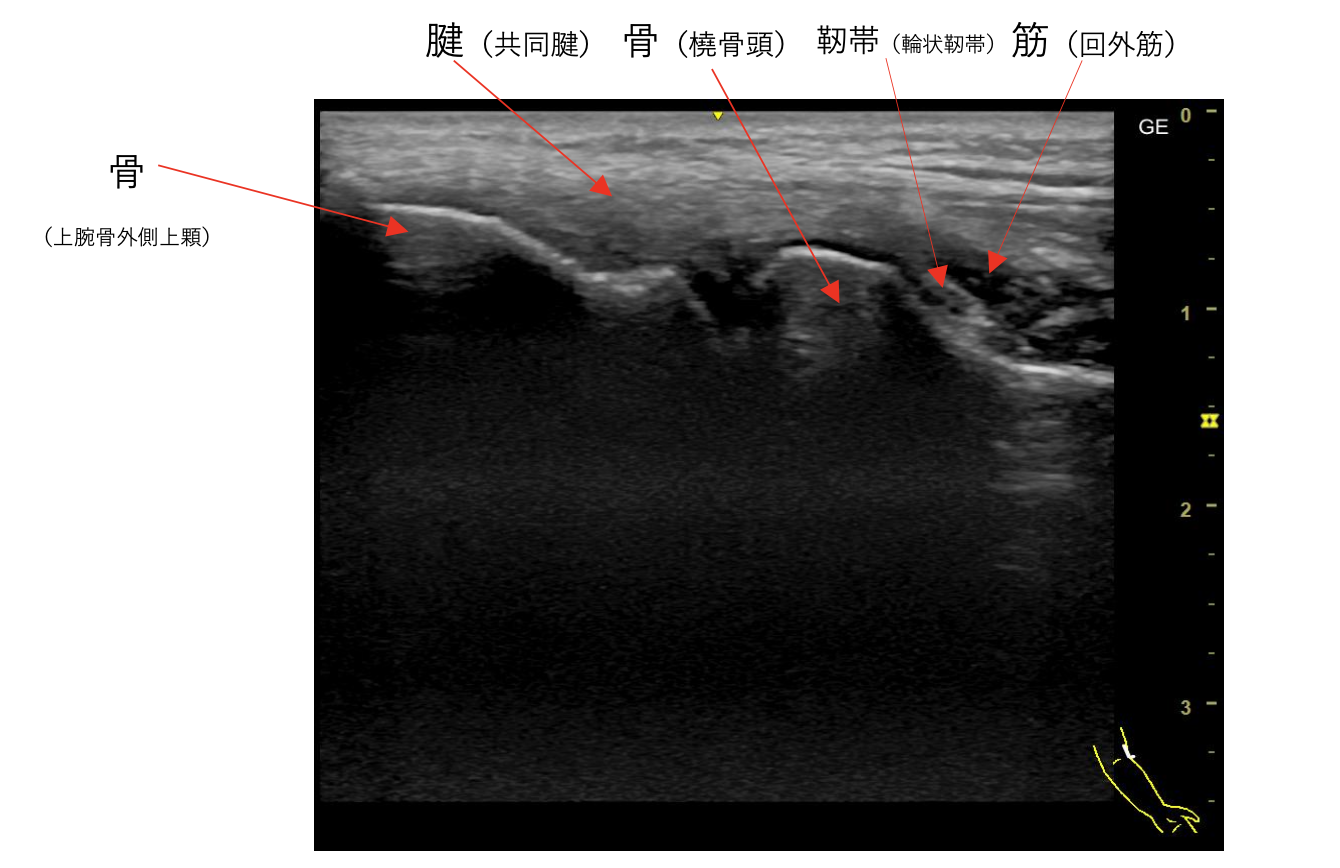

この画像は、肘関節の超音波エコー検査の実際の画像です。

この画像では、超音波エコー検査の特徴がよく表れています。

・骨は白く明るい線として表示され、その下は音波が通らないため黒く映る

・軟部組織(腱、靭帯、筋肉)は様々な濃淡のグレースケールで表示される

・リアルタイムで動的な観察が可能で、関節の動きに伴う構造の変化を確認できる

このような詳細な画像により、肘関節の炎症、腱の損傷、靭帯の異常などを診断することができます。